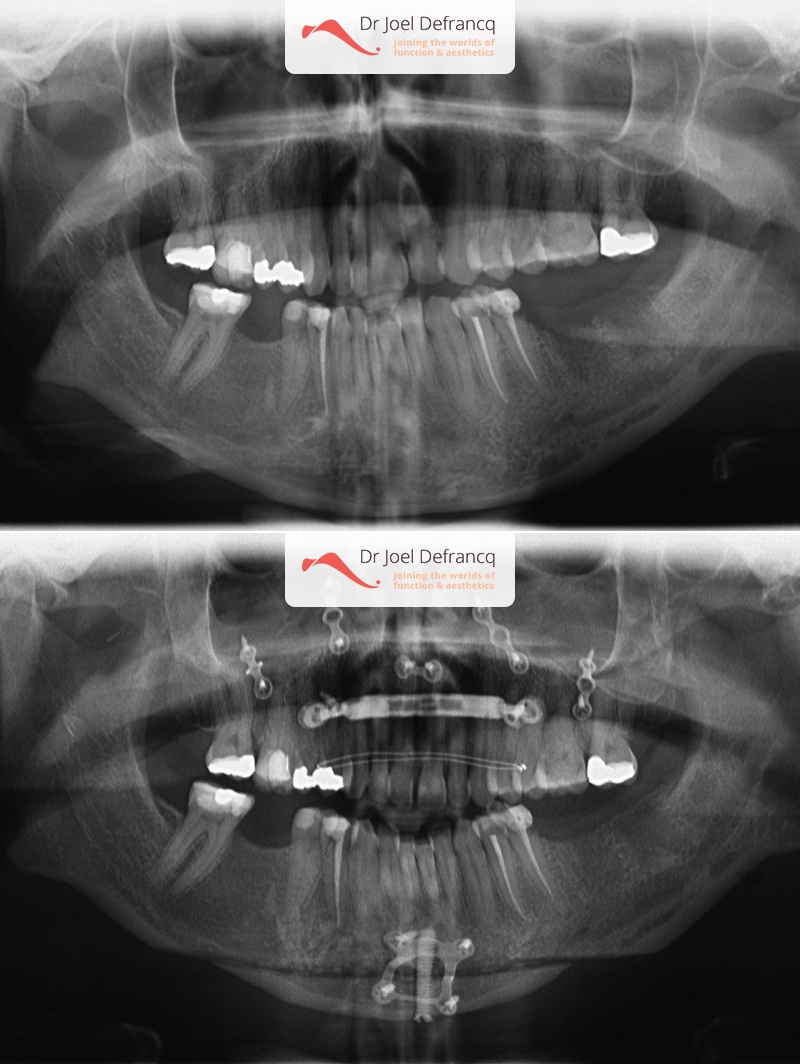

Dentale diagnose

- Klasse I

Kaakchirurgie

- Vertikale verkorting bovenkaak (Le Fort I)

- Kinchirurgie

- Verbreden bovenkaak (Smile distractor)